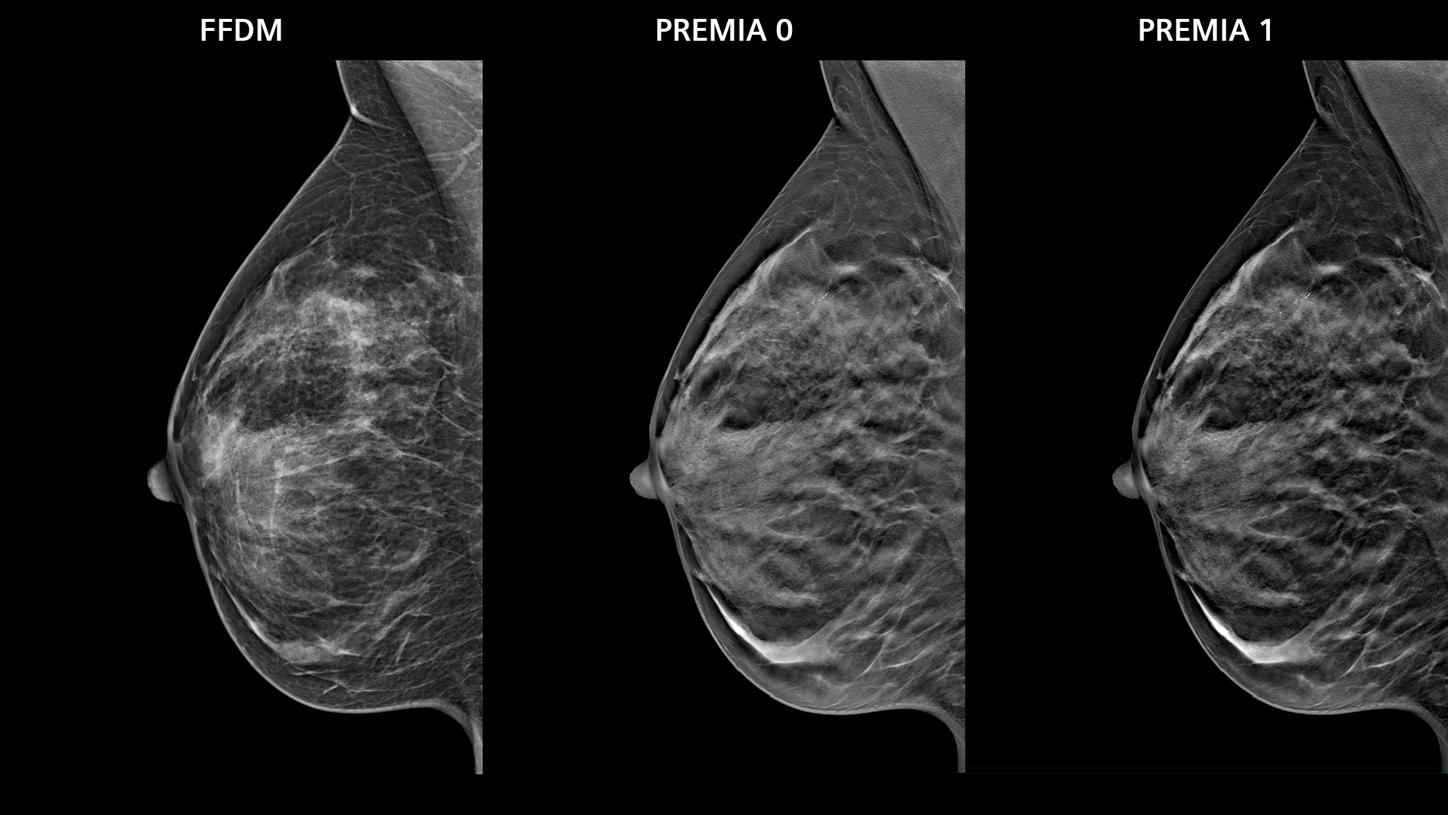

- PREMIA image reconstruction:

Improved image reconstruction framework- Reduce artifacts and enhance visibility of calcifications and lesions

- Comfortable transition from 2D and narrow-angle systems, thanks to customizable image impressions